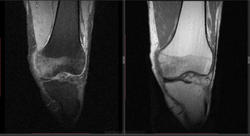

Мужчина 1963 г.р. Жалуется на боль в левом коленном суставе около 6 мес, в последний месяц стало совсем тяжко. Со слов заболел зимой, когда во время прогулки коленки сильно замерзли. Сам думаю на асептический некроз, но смущает множественность поражения.

Дмитрий, я в заболеваниях суставов не дока, но трабекулярный отек вкупе с выпотом может быть обусловлен воспалительными изменениями , но полностью начальные проявления аваскулярного некроза не могу отрицать.

я бы не поставил аваскулярный некроз. если исключена травма, дифференцировать с артритом.

Хрящ не поврежден, для артрита...